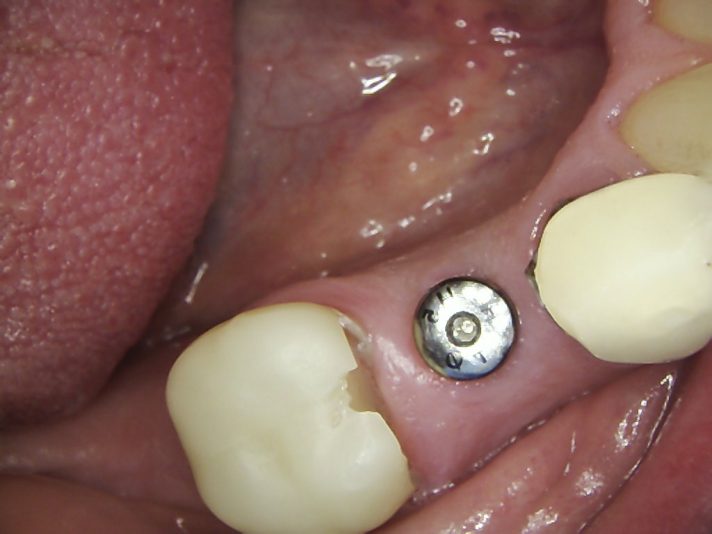

Hi, this implant was placed in June 2024. I have 3PAs (one from day of placement, one month later, and 9 month later). The intraoral picture of the soft tissue is from yesterday and tissue looks great… patient has no discomfort/pain either. She did have some discomfort between 2-3rd week after placement but subsided after taking antibiotics. On the one month xray, I may have missed the radioluency starting in apical 1/3.

Yesterday, I tapped the HA with the end of my mirror and wiggled the implant with no pain nor any perceptible movement. I am very suspicious, of course, about the radiolucency surrounding the apical 1/2 of the implant and am almost certain that the implant has failed (right?). I have removed failed implants at about 4 weeks (came out easily since still has not osseointegrated) but not at 9 months out…